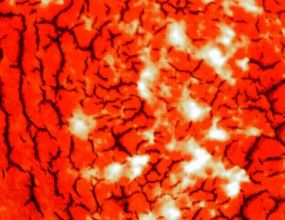

Droog Bloed Analyse

Kom je voor tweede analyse, dan kan je bij de tweede analyse kijken of je bloed verbeterd is door eventuele aanpassingen in je levensstijl of het gebruik van de aanbevolen supplementen.